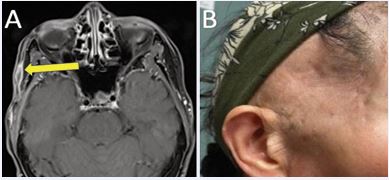

Contrast-enhanced face magnetic resonance imaging (MRI) obtained four months post-treatment demonstrated marked reduction in lesion size to 1.6 cm (Figure 3A).

https://www.jscimedcentral.com/public/assets/images/uploads/image-1766379045-1.JPG

Figure 3 (A) Contrast-enhanced face MRI four months post-treatment demonstrating significant treatment response. (B) Treated right temporal scalp at one-year post-treatment demonstrating excellent cosmetic outcome without clinical evidence of disease recurrence.

Routine surveillance MRI performed every six months thereafter showed stable findings with no evidence of local recurrence during two years of follow-up. No late toxicities, including nerve damage, fibrosis, or skin changes, were observed (Figure 3B).